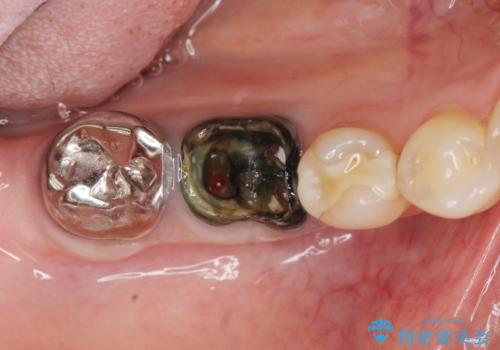

- 銀歯が取れてしまい、治療を希望され来院されました。

歯には大きな穴が開き、虫歯も大きくなってしまい残すことが難しいような状況であったため抜歯を余儀なくされました。